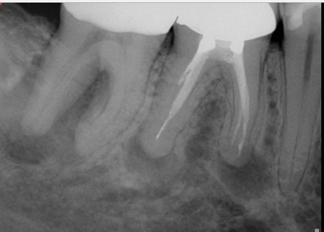

(7.) One-year follow-up periapical and bitewing radiographs demonstrating the absence of apical pathosis or furcal pathosis at the site of

the perforation.

Figure 7

(8.) One-year follow-up periapical and bitewing radiographs demonstrating the absence of apical pathosis or furcal pathosis at the site of

Figure 8